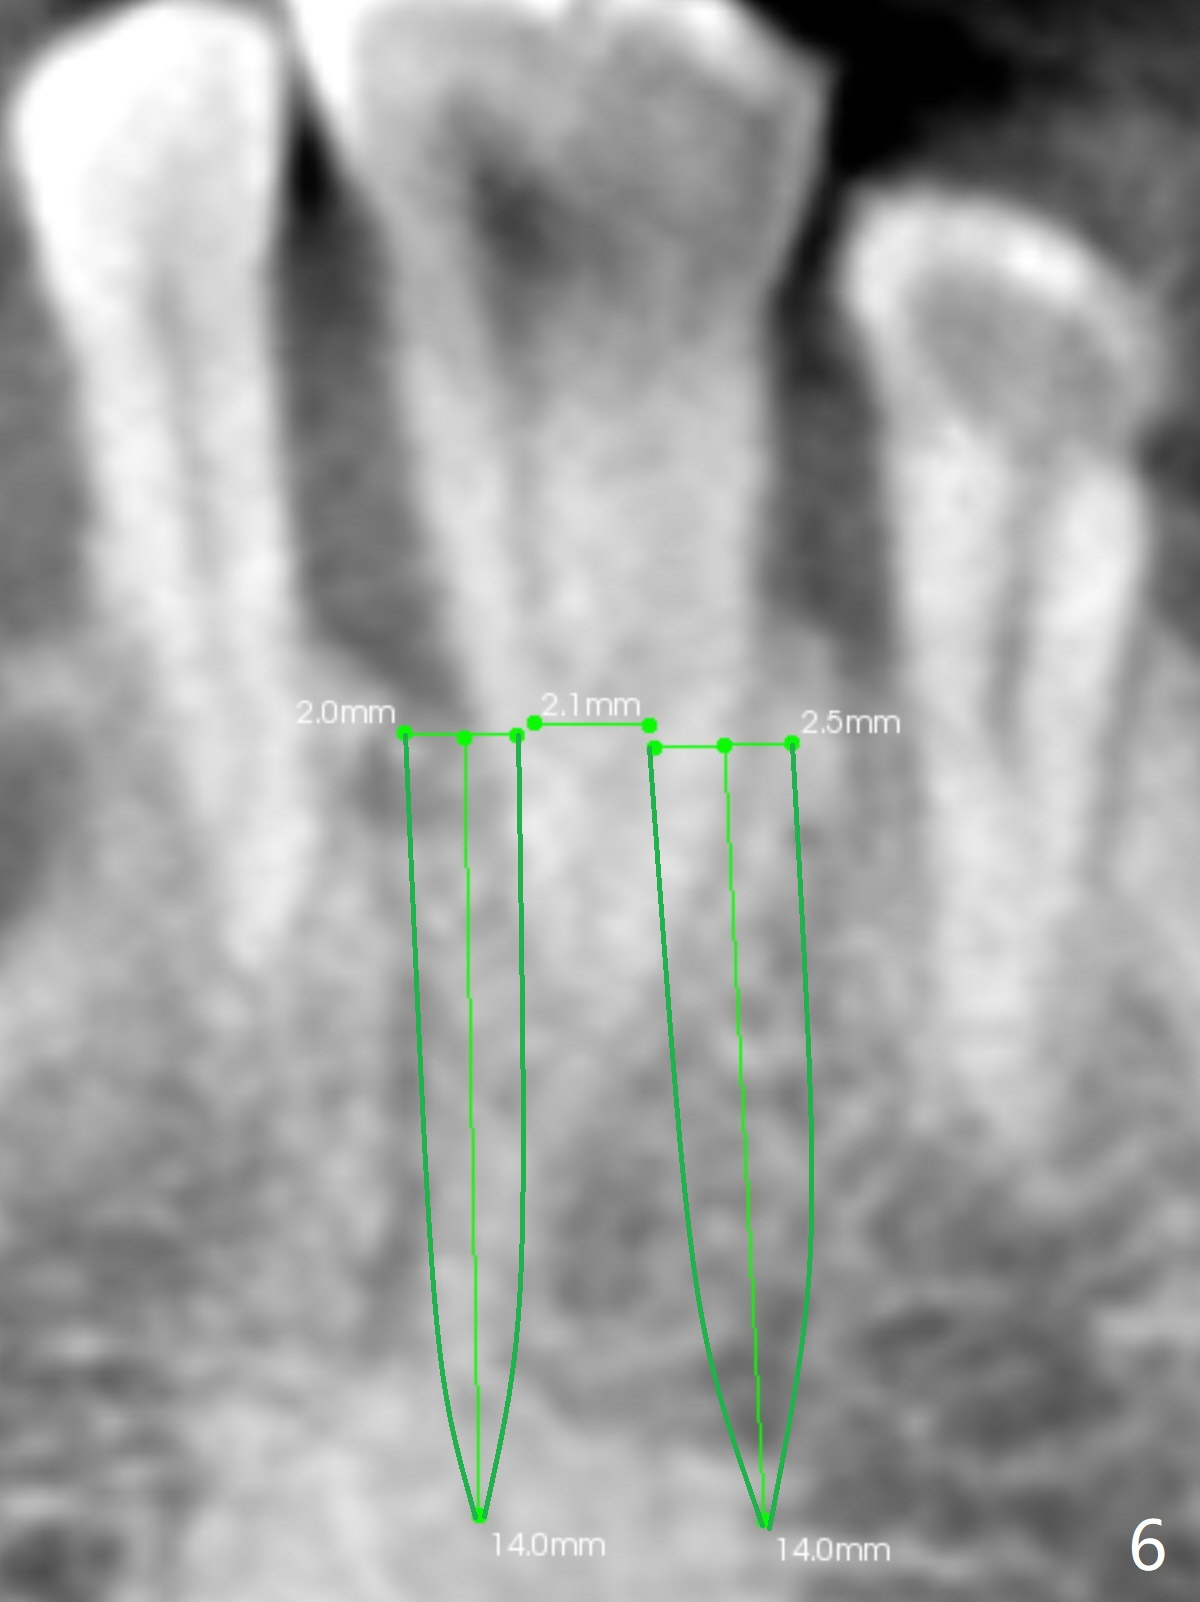

In fact, #22/23 mesiodistal width is ~ twice of that of an incisor (Fig.5). It is apparently more proper to place two smaller 1-piece implants (Fig.6) or a larger 2-piece one (Fig.7,8 (change to tissue-level one)).